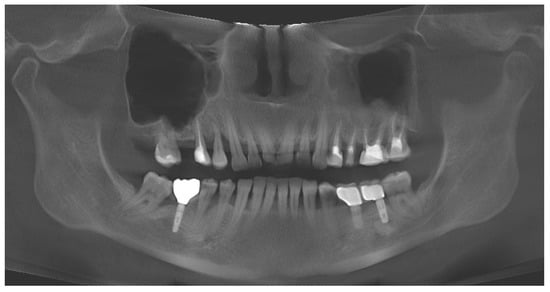

3.1. Case No. 1

3.2. Case No. 2